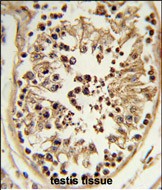

IHC 1/100-1/500 Human,Mouse,Rat

ImmunogenThis CHPF antibody is generated from rabbits immunized with a KLH conjugated synthetic peptide between 327-354 amino acids from the Central region of human CHPF.